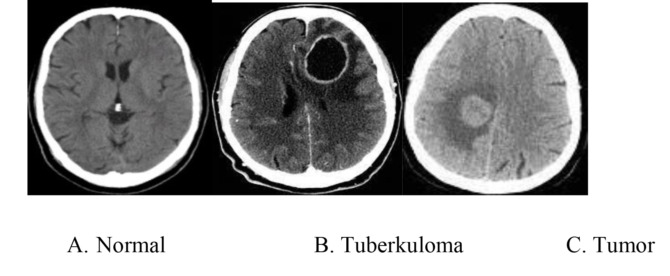

Pemeriksaan radiologis yang digunakan  untuk mendeteksi kelainan tersebut antara lain dengan computed tomography  (CT) scan. Pada pemeriksaan radiologis, tuberkuloma sering menyerupai gambaran tumor otak, maka diagnosa pasti baru dapat ditegakkan berdasarkan pemeriksaan histopatologi dan mikrobiologi paska operasi.

Keterangan gambar:

Gambar A: gambaran normal  CT Scan kepala

Gambar B: tuberkuloma sesudah pemberian kontras, tampak lesi berbentuk cincin dengan area hipodens/kehitaman di tengah, dengan dinding yang menyerap kontras disertai  area yang sembab disekeliling nya

Gambar C: tampak lesi berbentuk nodul yang menyerap kontras, kadang disertai sembab/edemadi sekitarnya